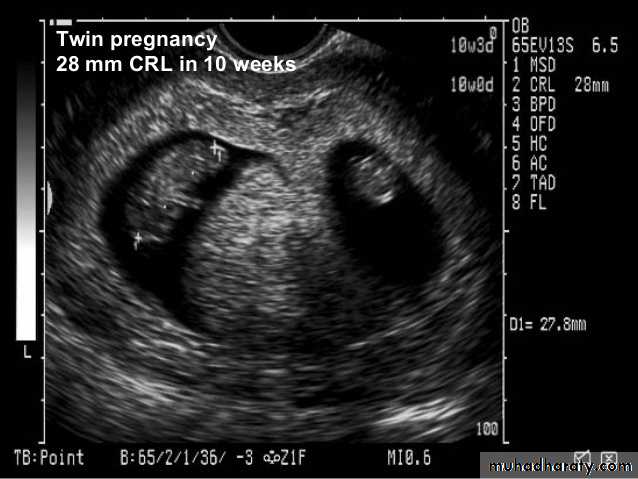

BPD together with head circumference (HC), abdominal circumference (AC), and femur length (FL) are computed to produce an estimate of fetal weight. In the second trimester this may be extrapolated to an estimate of gestational age and an estimated due date (EDD) .